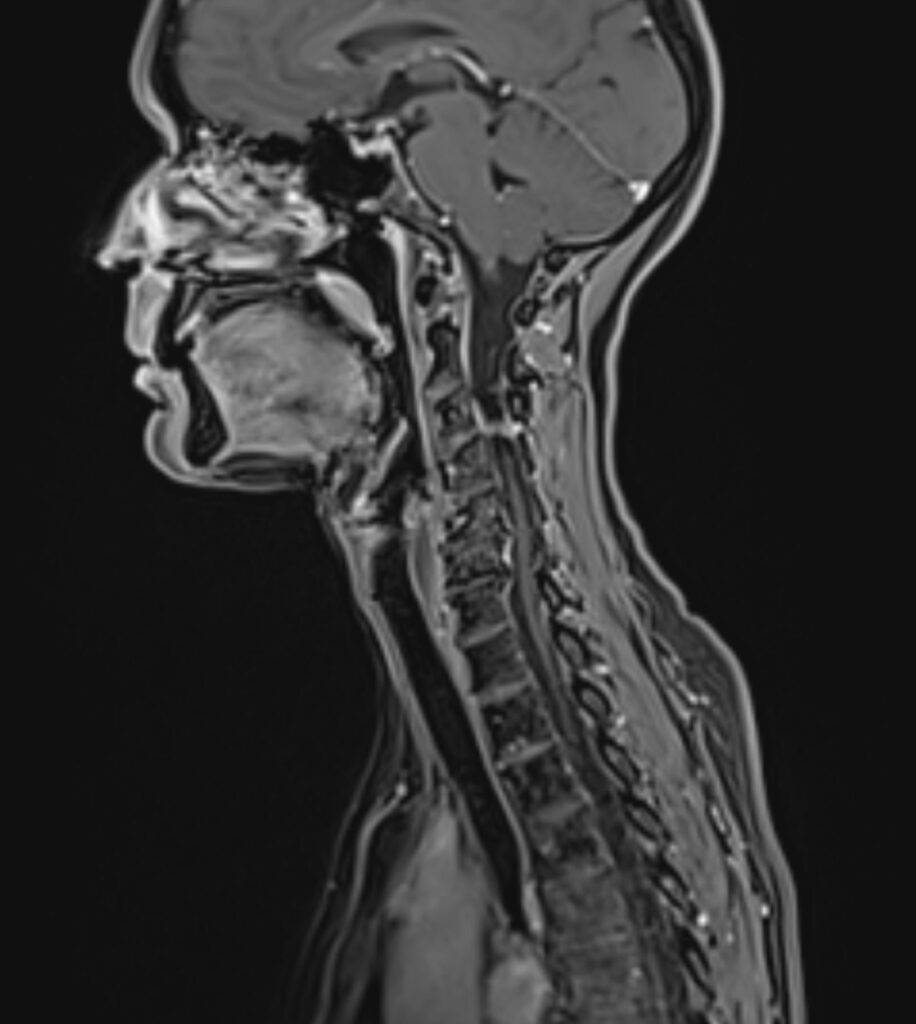

Die Magnetresonanztomographie der Halbwirbelsäule, kurz MRT HWS genannt, ist ein bildgebendes Diagnoseverfahren. In einer MRT HWS ist es möglich, den Bereich der Halswirbelsäule mit allen anatomischen Strukturen bildlich darzustellen. Besonders im Falle eines Verdachts auf Bandscheibenvorfall im Bereich der HWS ist eine Magnetresonanztomographie die bevorzugte Diagnosemethode.

Jährlich erleiden 180.000 Personen einen Bandscheibenvorfall. Dieser kann sich in der Halswirbelsäule (HWS), in der Brustwirbelsäule (BWS) oder in der Lendenwirbelsäule (LWS) ereignen.

Falls Sie unter Schmerzen im Nackenbereich leiden, diese bereits in die anliegenden Bereiche ausstrahlen und sogar schon starke Kopfschmerzen verursachen, ist eine MRT der Halswirbelsäule eine Möglichkeit die Ursache für Ihre Schmerzen zu finden.

Bei einer MRT der Halswirbelsäule wird der Nackenbereich abgebildet. Die unterschiedlichen anatomischen Strukturen können präzise dargestellt werden und dienen der Beurteilung von Erkrankungen der Halswirbelsäule.

Was sieht man alles auf einer MRT HWS?

| Wirbelkörper | Einzelne Wirbelkörper, Form und Struktur |

| Bandscheiben | Bandscheiben zwischen den Wirbeln |

| Rückenmark und Nervenwurzel | Gesamter Wirbelkanal |

| Weichteile | Muskeln, Bänder, Lymphknoten |